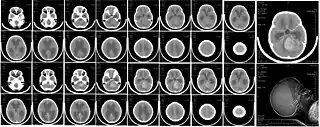

![]() Imagen típica de un meduloblastoma. Resonancia magnética secuencia T2WI de un niño. | ||

La mayoría se visualizan como una lesión sólida que realza con contraste al realizar la tomografía axial computarizada (TAC) o resonancia magnética (RMN) aunque el aspecto puede variar y verse algo difuso principalmente en niños menores de 3 años. La localización del tumor suele ser sobre la línea media del cuarto ventrículo (localizaciones laterales suelen ser más común en adultos). Es muy probable que se observe de hidrocefalia. Su principal diagnóstico diferencial al valorar las imágenes es el ependimoma.

- TAC: Hiperdenso (alta celularidad); Contraste: aún más hiperdenso. Calcificaciones en el 20% de los casos.

- RMN cerebral: T1WI: hipo a isointenso; T2WI: heterogéneo por tumor quístico, vasos y calcificaciones. Contraaste: marcada hiperintensidad.